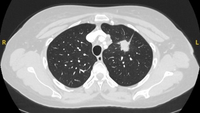

Computed tomography (CT) sections from two cases with benign perifissural nodules. Note the smooth margins and the normal undisturbed adjacent fissure

From the collection of Dr George Tsaknis, MD, PhD, FRCP(London), MRQA, MAcadMEd, PGCert; used with permission